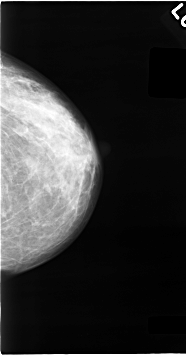

C_0063_1.LEFT_CC

LEFT_CC LINES 4632 PIXELS_PER_LINE 2416 BITS_PER_PIXEL 12 RESOLUTION 50 NON_OVERLAY